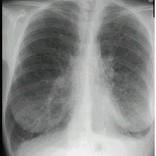

问题 女,33岁,气短伴咳嗽2周,CT检查如图,最可能的诊断为 ( )

选项 A.肺间质纤维化 B.肺淋巴管肌瘤病 C.慢性支气管炎并感染 D.硅沉着病 E.肺囊肿并感染

答案 B